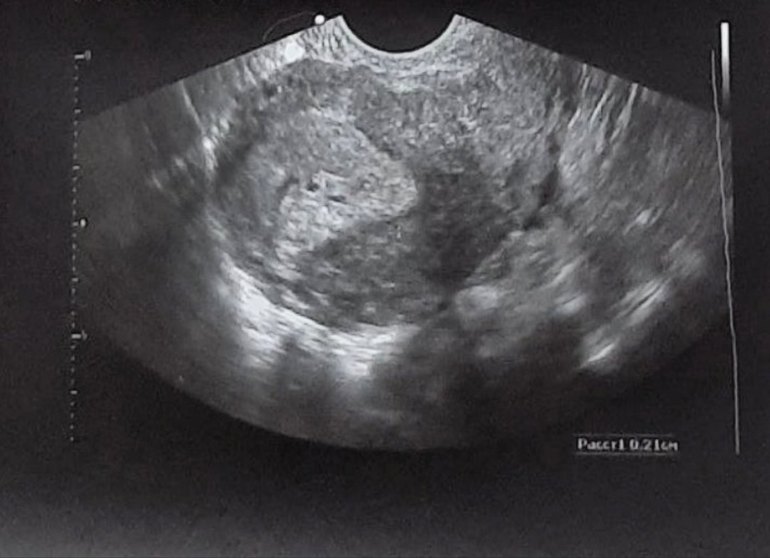

Гематома или второе плодное яйцо?

УЗИ, КТГ, доплер, скрининг, ХГЧ и другие анализыДевочки, узи делала неделю назад. На повторное завтра, страшно...и все же решила написать, вдруг у кого та уже было. Как вам кажется, что это рядом с плодным яйцом?

П.с. беременность пятая, в роду двойни нет. Врач ничего не сказала.